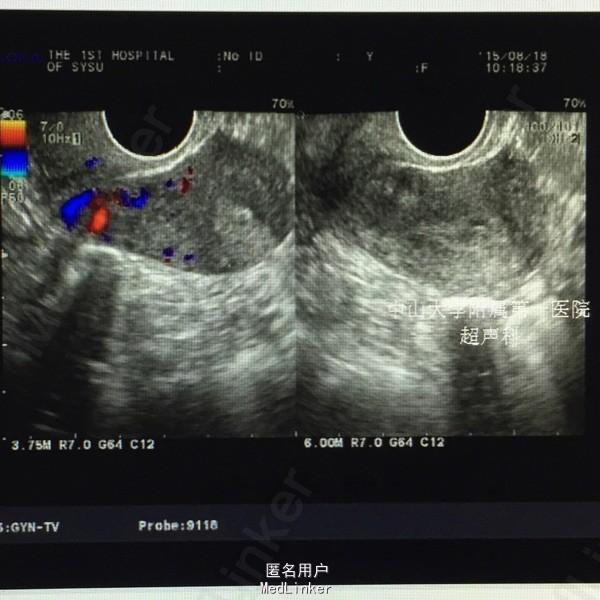

妇查:无异常。 辅查:2015-05-28外院行输卵管三维超声造影检查,结果提示“左侧输卵管通而不畅,右侧输卵管近段阻塞”。 2015-8月我院妇科B超示: 子宫内膜厚径9mm, 肌层回声欠均,子宫前壁低回声区9mm×7mm,考虑小型子宫肌瘤。